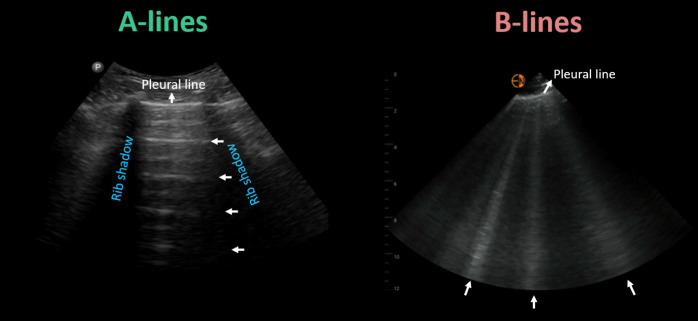

Point-of-care ultrasonography (POCUS), particularly venous excess ultrasound (VExUS) is emerging as a valuable bedside tool to gain real-time hemodynamic insights. This modality, derived from hepatic vein, portal vein, and intrarenal vessel Doppler patterns, offers a scoring system for dynamic venous congestion assessment. Such an assessment can be crucial in effective management of patients with heart failure exacerbation. It facilitates diagnosis, quantification of congestion, prognostication, and monitoring the efficacy of decongestive therapy. As such, it can effectively help to manage cardiorenal syndromes in various clinical settings. Extended or eVExUS explores additional veins, potentially broadening its applications. While VExUS demonstrates promising outcomes, challenges persist, particularly in cases involving renal and liver parenchymal disease, arrhythmias, and situations of pressure and volume overload overlap. Proficiency in utilizing spectral Doppler is pivotal for clinicians to effectively employ this tool. Hence, the integration of POCUS, especially advanced applications like VExUS, into routine clinical practice necessitates enhanced training across medical specialties.